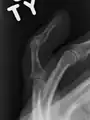

X-ray showing fracture at the insertion of the extensor tendon

A mallet finger usually results from overbending of the finger tip.[3] Typically this occurs when a ball hits an outstretched finger and jams it.[3] This results in either a tear of the tendon or the tendon pulling off a bit of bone.[3] The diagnosis is generally based on symptoms and supported by X-rays.[3]

The diagnosis is generally based on symptoms and supported by X-rays.[3] The injury can be accompanied by swelling and ecchymosis.[4]